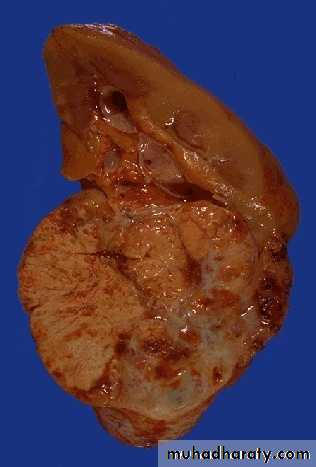

Nephroblastome (Wilm's Tumour)Morphologic features

Tumors are solitary, well circumscribed, rounded and of soft in consistency.The size is variable, with a median weight of 550gm.

The cut section is predominantly solid and pale gray or tan and often exhibits areas of cystic change, necrosis, and hemorrhage.

Multicentric foci are found in 7% of cases.